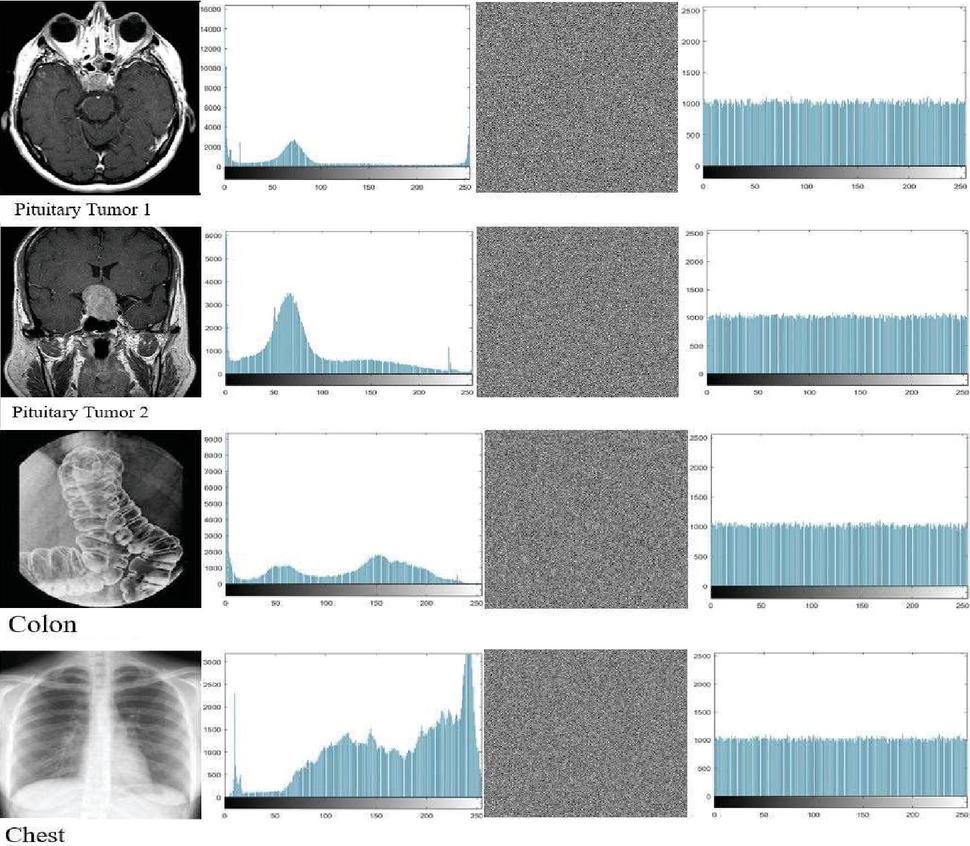

5.2 Histogram Analysis

A histogram is an analytical tool that represents grayscale levels on the horizontal axis and pixel density on the vertical axis to provide a comprehensive statistical description of an image’s content. Notably, histogram columns for encrypted images tend to have a uniform distribution to prevent attackers from discerning the encrypted content, as opposed to the different headers of histogram columns describing normal image content [19, 21, 24, 38, 39]. Figure 4 illustrates the effect of the proposed encryption algorithm on the test images, where the regularity of the graph columns of the encrypted images indicates the algorithm’s resistance to statistical attacks.

images

Figure 4 Histograms accompany both the unencrypted and encrypted images.